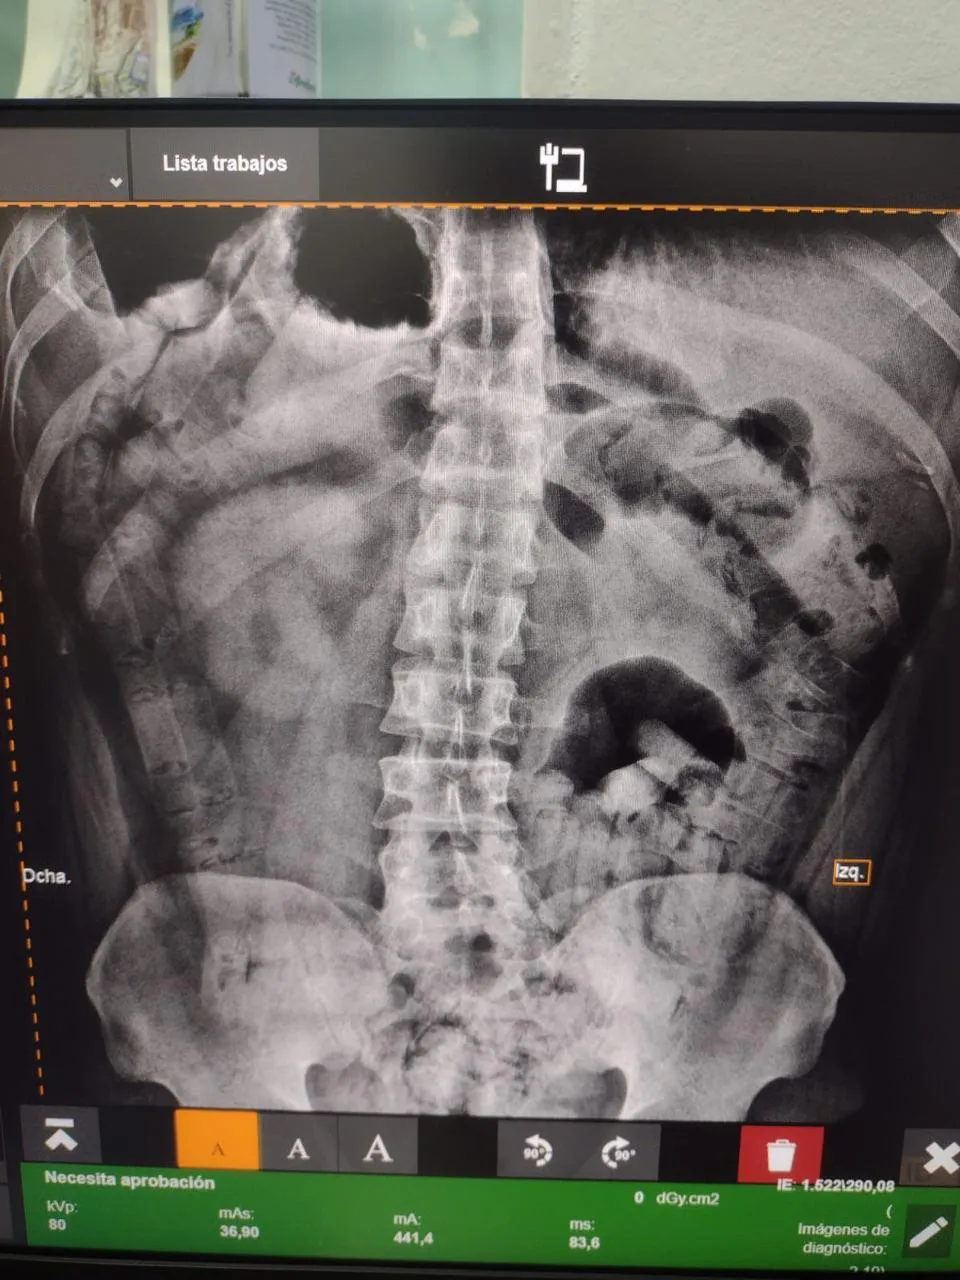

Los funcionarios comunicaron el hecho al Juzgado Federal de Tucumán, que ordenó el traslado de ambas ciudadanas a un centro de salud, donde fueron sometidos a pruebas de rayos X. Se logró observar cuerpos extraños en sus estómagos. Con el paso de los días bajo revisión médica expulsaron 206 cápsulas alcanzando 2 kilos de cocaína.